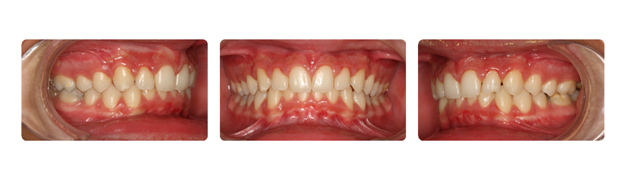

| فک پایین بیمار جلوتر از فک بالا قراردارد وهمچنین دندانهای فک بالا پشت دندانهای پایین قرار گرفته است ودندانهای نیش فک بالا بصورت نهفته می باشد: |

![]() |

| دندان نهفته ی نیش سمت راست در قسمت کام وسمت چپ در زیر لب و بالای دندانها قرار دارد که توسط جراح لثه روی آن برداشته شده وتوسط ارتودنسی و براکتها به جای برده می شود: |